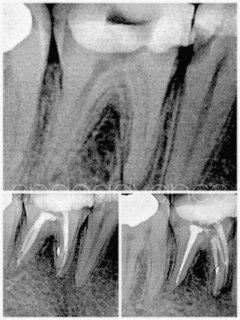

Αρχική ενδοδοντική θεραπεία σε 2ο κάτω γομφίο